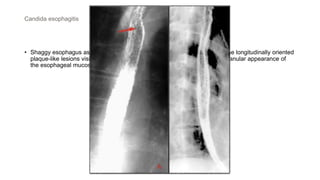

• Shaggy esophagus associated with Candida infection , image "A" depicts the longitudinally oriented

plaque-like lesions visible in Candida esophagitis , image "B" depicts the granular appearance of

the esophageal mucosa secondary to edema and inflammation